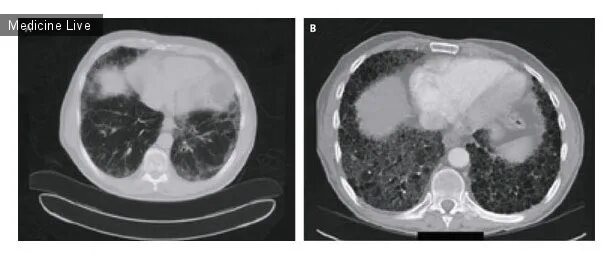

Прогрессирующий фиброз